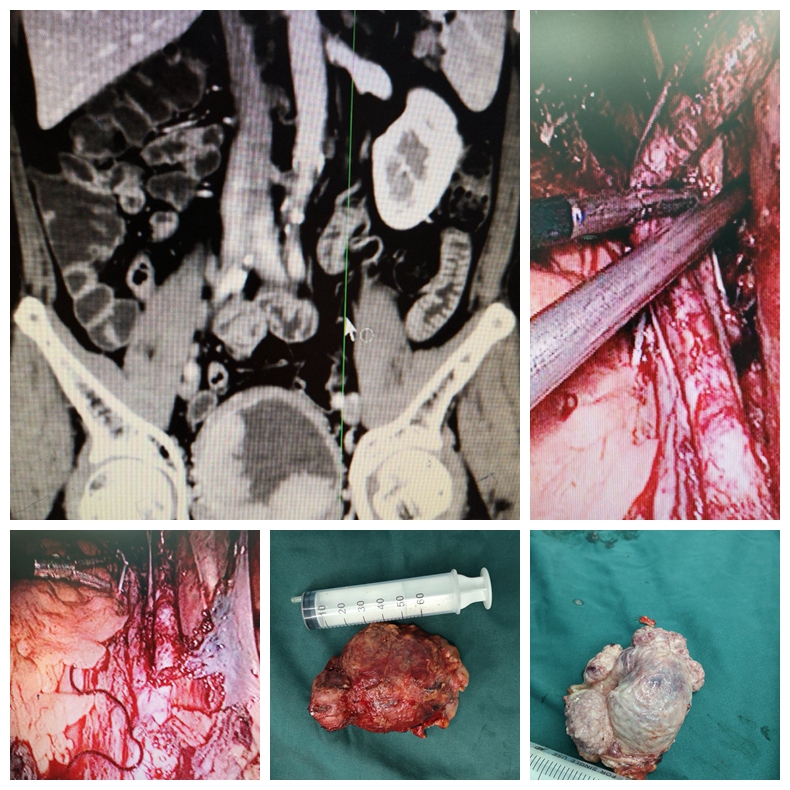

开放性左肾癌根治性切除+静脉癌栓取出+腹膜后淋巴结清扫术治疗左肾癌合并静脉癌栓、

腹膜后淋巴结转移的病例

科室积致力于泌尿外科微创技术的创新和优化。在广泛开展腹腔镜肾癌根治术、肾部分切除术、前列腺癌根治术、全膀胱切除术及肾上腺肿瘤切除术等基础上,进一步扩大腹腔镜技术的覆盖范围,开展腹腔镜下腹膜后和盆腔扩大淋巴结清扫术等高难度手术。推动外科微创化与加速康复外科(ERAS)的紧密结合,打造成特色、优势技术,受到广大患者认可。泌尿系统结石疾病的诊治是我科的传统优势项目,保持着省内先进水平。我科应用经皮肾镜技术开展了一些高难度的肾结石手术,如严重脊柱畸形患者的肾结石、孤立肾肾结石、无肾积水的肾结石、马蹄肾肾结石等,而且手术均取得成功。泌尿系肿瘤的发病率逐年升高,其防治任重而道远。我科积极开展复杂性泌尿系肿瘤的诊治,尤其是巨大肾上腺肿瘤、巨大肾肿瘤、孤立肾较大肾癌的保留肾脏手术等。同时积极开展泌尿系肿瘤的防治研究,重点进行泌尿系肿瘤病因学的研究,尤其是寻找膀胱癌、肾癌和前列腺癌相关功能基因,从基因学角度寻找肿瘤特异标记物,提高泌尿系肿瘤早期诊断水平,并为进一步基因治疗提供基础。前列腺增生作为老年男性常见疾病一直以来是我们重点研究的方向和医疗特色之一。随着外科技术的不断进步及新的医疗设备的不断涌现和完善,TURP的金标准地位逐渐受到挑战,如经尿道钬激光前列腺剜除术技术日臻完善,大有取代TURP之势。目前我科已积极开展经尿道钬激光在良性前列腺增生治疗中的应用,取得了良好的治疗效果。我科针对目前男性疾病诊治需求量迅速增加的现状,积极开展男科的特色诊疗,范围包括男子勃起功能障碍、早泄、男性不育症、精索静脉曲张、血精、阴茎硬结症、睾丸附睾疾病、男子生殖系统内分泌疾病等。开科以来典型手术介绍如下: